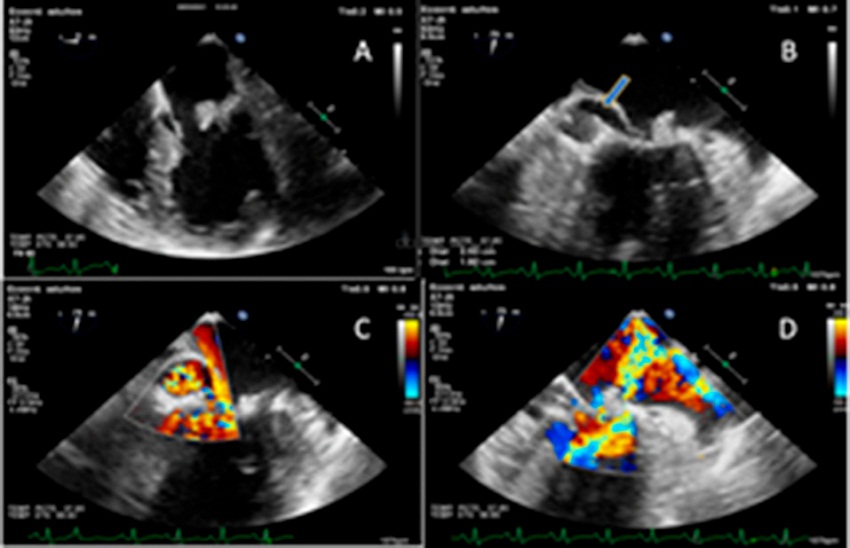

En el ETT se observaron imágenes móviles en ambas valvas de la válvula mitral, de 20 mm de longitud aproximadamente. En el eco transesofágico se evidenció una imagen cavitada en la valva posterior mitral de 2,53 cm × 1,92 cm de diámetro, con flujo en su interior compatible con pseudoaneurisma valvular e insuficiencia mitral moderada que se interpretó como secundaria a alteración de la estructura valvular. (Figura 2)